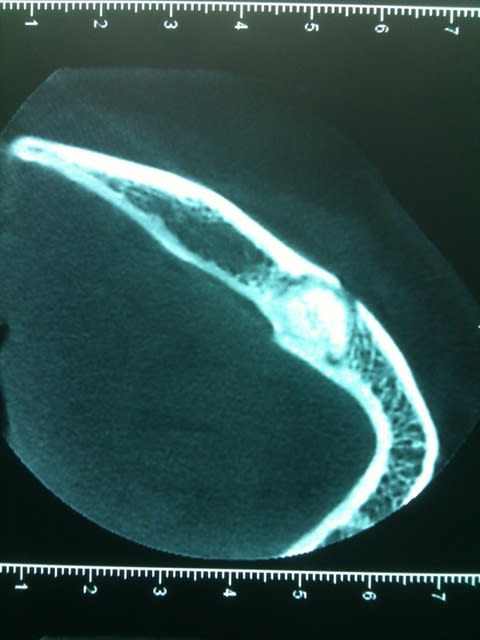

Un confrère savant pourrait il me donner un diagnostic et une CAT concernant le tissu osseux en regard de 45 ?

La racine parait fracturée mais à part une légère douleur à la pression, rien d'autre..

çà semble être une ostéïte condensante...